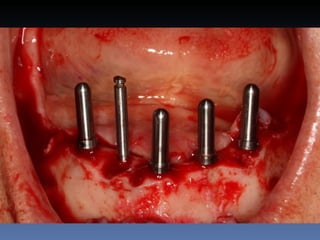

BOX 2 Maria SeemagennBorges Idade – 49 anos Sexo – Feminino Raça – Caucasiana ASA – II Data- 24-04-2012 Diagnóstico: Desdentada total mandibula Plano de tratamento: Instalação de 5 implants endo- ósseos - “Protocolo Branemark”, com carga imediata.

Diagnóstico: Desdentada

total mandibula

Plano de tratamento: Instalação de 5 implants endo-

ósseos - “Protocolo Branemark”, com carga imediata.

BOX 5 Rute GomesMealha Idade – 70 anos Sexo – Feminino Raça – Caucasiana ASA – I Data- 24-04-2012 Diagnóstico: Desdentada mandibular posterior. Plano de tratamento: Exondontia de todos os dentes mandibulares existentes, instalação de 5 implantes endo-ósseos – Protocolo Branemark, com carga imediata.

Plano de tratamento: Exondontia de todos os dentes

mandibulares existentes, instalação de 5 implantes

endo-ósseos – Protocolo Branemark, com carga

imediata.